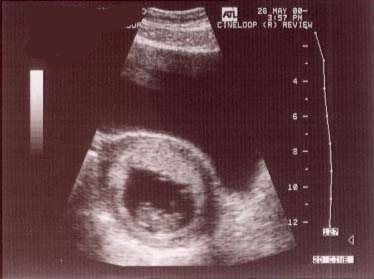

5/26/2000